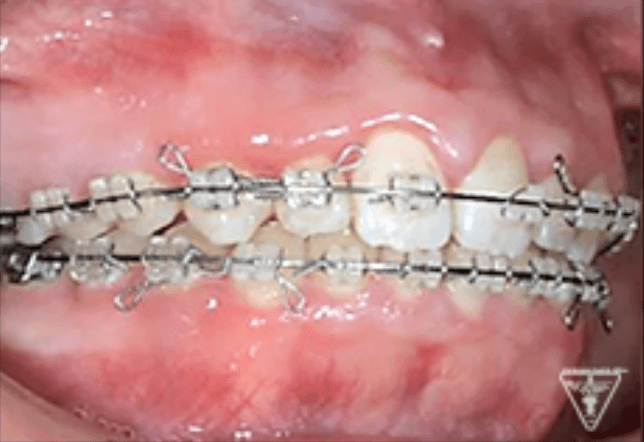

矯正器具 装着時の治療過程

初期